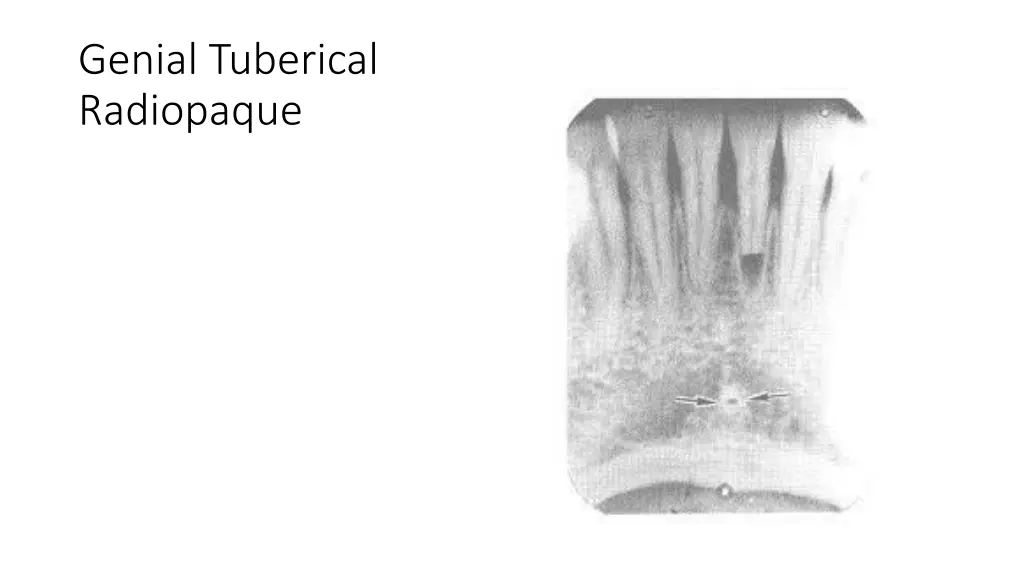

Genial Tuberical Radiopaque